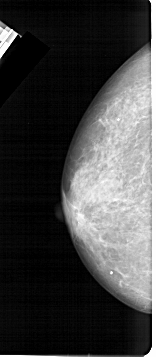

A_1473_1.RIGHT_CC

RIGHT_CC LINES 4636 PIXELS_PER_LINE 2116 BITS_PER_PIXEL 12 RESOLUTION 43.5 OVERLAY